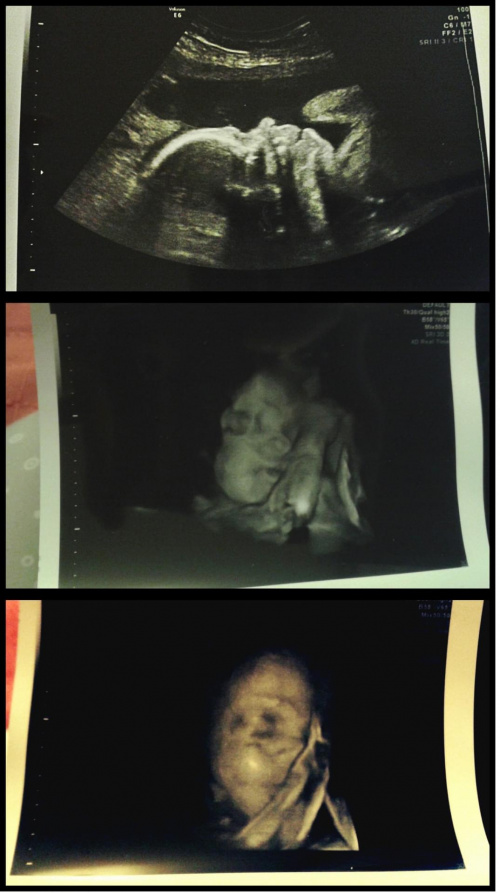

Julek waży już 1220g

jest ułożony pośladkowo czyli zmienił pozycję. Machał do nas rączkami, uśmiechał się, połykał wody płodowe, a najlepsze było jak pani dr włączyłą obraz 3D, a tam buźka, obok niej rączka, a obok nóżka ze stópką założoną za główkę

mały akrobata nam rośnie

Szyjka ma 34mm, jest twarda i zamknięta. Szew pięknie trzyma.

Kolejna wizyta 9.02, a 10.02 kładę się na 3 dni do szpitala na podanie sterydów na płucka dla dziecka.

Wizyta dziś wyjątkowo długa tzn samo usg bardzo dokładne, pośmialiśmy się jak Julek kopał w aparat podczas usg

A to mój ufoludek :